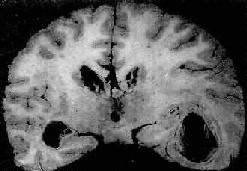

肉眼观,脑脊膜血管高度扩张充血,病变严重的区域,蛛网膜下腔充满灰黄色脓性渗出物,覆盖着脑沟脑回,以致结构模糊不清(图16-10),边缘病变较轻的区域,可见脓性渗出物沿血管分布。在渗出物较少的区域,软脑膜往往略带混浊。脓性渗出物可累及大脑凸面矢状窦附近或脑底部视神经交叉及邻近各池。由于炎性渗出物的阻塞,使脑脊液循环发生障碍,可引起不同程度的脑室扩张

化脓性脑膜炎

图16-10 化脓性脑膜炎

蛛网膜下腔内有多量脓液堆积以致大部分脑表面的沟回结构不清;脑膜血管高度扩张充血